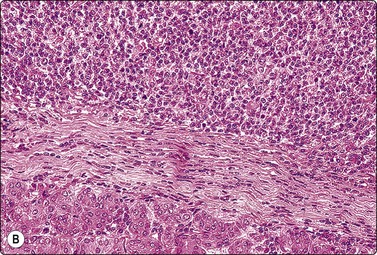

Paraganglioma (carotid body and glomus jugulare tumors) (Figs 4.11-4.13)5,50-52

image image

Fig. 4.13 Paraganglioma (atypical)

(A) Smear showing prominent anisokaryosis but a uniformly bland chromatin pattern (MGG, HP); (B) Tissue section of the same case (H&E, IP).

The cytological pattern is suggestive of an endocrine neoplasm and, given the anatomical site, the main differential diagnosis is a thyroid tumor. A follicular arrangement of the tumor cells may suggest a follicular carcinoma, but the fine red cytoplasmic granulation, the characteristic anisokaryosis and the presence of spindle cells closely resemble medullary carcinoma, and this is the main differential diagnosis (Fig. 4.12). Immune markers are helpful. Cells of paraganglioma stain positively for neuroendocrine markers. Staining for calcitonin is negative in most cases, but can occasionally be positive. Cytokeratin, thyroglobulin and TTF1 are negative. Intranuclear cytoplasmic inclusions as in papillary and some other carcinomas of the thyroid can be found in some paragangliomas.50 Knowledge of the exact anatomical site is obviously important. However, paraganglioma can occur in atypical locations including, although rarely, the thyroid. For example, one of our cases diagnosed by FNB had a tumor in the tonsillar region, clinically thought to be a deep parotid tumor (Fig. 4.11); another had a supraclavicular mass diagnosed clinically as lymphadenopathy. Both were histologically confirmed as paragangliomas.

Paraganglioma with a spindle cell pattern can mimic other spindle cell tumors in the neck such as spindle cell medullary carcinoma of thyroid and soft tissue tumors. Nuclear pleomorphism can sometimes be prominent enough to suggest malignancy (Fig. 4.13).5 As in other endocrine tumors, pleomorphism is not a reliable indicator of malignancy, mitotic rate and evidence of necrosis are better related to clinical behavior, and metastasis is the only definitive proof.

Paragangliomas are extremely vascular lesions and the aspirate often appears to be pure blood. If this is the case, smears may be non-diagnostic but diagnostic tissue fragments can sometimes be found in a cell block.